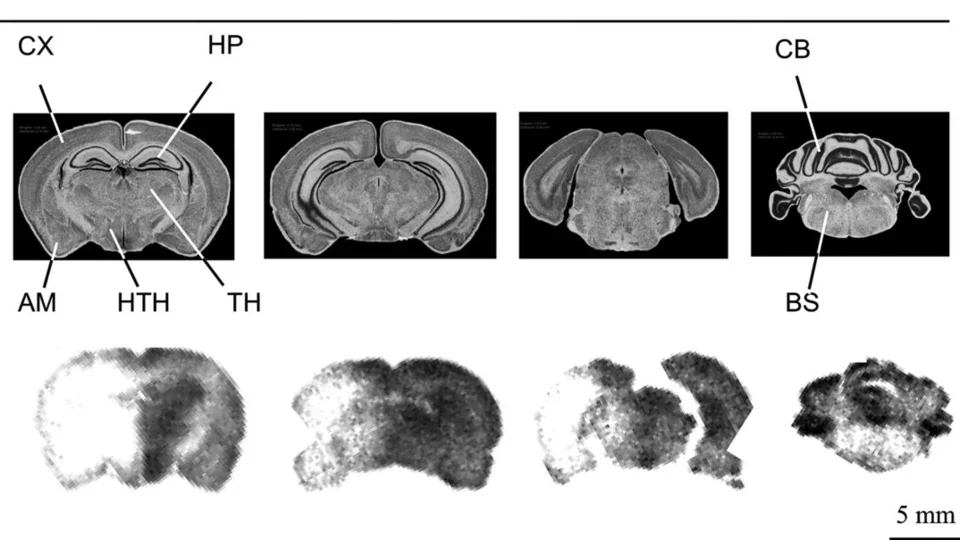

Breadcrumb Home Applications Gallery Gallery Applications Videos Gallery Library of Recent Studies Cancer Biology Coupling IL-2 with IL-10 to mitigate toxicity and enhance antitumor immunity. Ahn et al. 2025. Cell Rep Med. PGC-1α drives small cell neuroendocrine cancer progression toward an ASCL1-expressing subtype with increased mitochondrial capacity. Varuzhanyan et al. 2024. Proc Natl Acad Sci U S A. 89Zr-ImmunoPET for the Specific Detection of EMP2-Positive Tumors. Chan et al. 2024. Mol Cancer Ther. 18F-Labeled brain-penetrant EGFR tyrosine kinase inhibitors for PET imaging of glioblastoma. Narayanam et al. 2023. Chem Sci. M2 isoform of pyruvate kinase rewires glucose metabolism during radiation therapy to promote an antioxidant response and glioblastoma radioresistance. Bailleul et al. 2023. Neuro Oncol. Spatial mapping of mitochondrial networks and bioenergetics in lung cancer. Han et al. 2023. Nature. Anti-PD-1/L1 lead-in before MAPK inhibitor combination maximizes antitumor immunity and efficacy. Wang et al. 2021. Cancer Cell. In vivo imaging of mitochondrial membrane potential in non-small-cell lung cancer. Momcilovic et al. 2019. Nature. Immunotherapy Low-dose exposure to PBDE disrupts genomic integrity and innate immunity in mammary tissue. Lamkin et al. 2022. Front Genet. Immuno-PET in Inflammatory Bowel Disease: Imaging CD4-Positive T Cells in a Murine Model of Colitis. Freise et al. 2018. J Nucl Med. ImmunoPET of Malignant and Normal B Cells with 89Zr- and 124I-Labeled Obinutuzumab Antibody Fragments Reveals Differential CD20 Internalization In Vivo. Zettlitz et al. 2017. Clin Cancer Res. Detection of immune responses after immunotherapy in glioblastoma using PET and MRI. Antonios et al. 2017. Proc Natl Acad Sci U S A. Neuroscience [18F]FDG-PET and [18F]MPPF-PET are brain biomarkers for the creatine transporter Slc6a8 loss of function mutation. Day et al. 2025. Sci Rep. Gene therapy for guanidinoacetate methyltransferase deficiency restores cerebral and myocardial creatine while resolving behavioral abnormalities. Khoja et al. 2022. Mol Ther Methods Clin Dev. Regional distribution of SGLT activity in rat brain in vivo. Yu et al. 2013. Am J Physiol Cell Physiol. [F-18]FDDNP microPET imaging correlates with brain Aβ burden in a transgenic rat model of Alzheimer disease: effects of aging, in vivo blockade, and anti-Aβ antibody treatment. Teng et al. 2011. Neurobiol Dis. Cardiology Preclinical evaluation of high-resolution CT, 18F-FDG, and 18F-NaF PET imaging for longitudinal monitoring of atherosclerosis. Tamboline et al. 2025. Eur J Nucl Med Mol Imaging. A humanized monoclonal antibody targeting an ectonucleotidase rescues cardiac metabolism and heart function after myocardial infarction. Li et al. 2024. Cell Rep Med. Invasive electrochemical impedance spectroscopy with phase delay for experimental atherosclerosis phenotyping. Chen et al. 2024. FASEB J. Changes in microarchitecture of atherosclerotic calcification assessed by 18F-NaF PET and CT after a progressive exercise regimen in hyperlipidemic mice. Hsu et al. 2021. J Nucl Cardiol. Statin Effects on Vascular Calcification: Microarchitectural Changes in Aortic Calcium Deposits in Aged Hyperlipidemic Mice. Xian et al. 2021. Arterioscler Thromb Vasc Biol. Statin Effects on Vascular Calcification: Microarchitectural Changes in Aortic Calcium Deposits in Aged Hyperlipidemic Mice. Xian et al. 2021. Arterioscler Thromb Vasc Biol. Effects of teriparatide on morphology of aortic calcification in aged hyperlipidemic mice. Hsu et al. 2018. Am J Physiol Heart Circ Physiol. Metabolism PPARγ-dependent remodeling of translational machinery in adipose progenitors is impaired in obesity. Siqueira et al. 2024. Cell Rep. Dietary control of peripheral adipose storage capacity through membrane lipid remodelling. Tol et al. 2025. Nat Metab. Drug Development Recent developments in translational imaging of in vivo gene therapy outcomes. Day et al. 2025. Mol Ther. A Glucose-Responsive Glucagon-Micelle for the Prevention of Hypoglycemia. Vinciguerra et al. 2024. ACS Cent Sci. A humanized monoclonal antibody targeting an ectonucleotidase rescues cardiac metabolism and heart function after myocardial infarction. Li et al. 2024. Cell Rep Med. An HK2 Antisense Oligonucleotide Induces Synthetic Lethality in HK1-HK2+ Multiple Myeloma. Xu et al. 2019. Cancer Res. A precision therapeutic strategy for hexokinase 1-null, hexokinase 2-positive cancers. Xu et al. 2018. Cancer Metab. Development of new deoxycytidine kinase inhibitors and noninvasive in vivo evaluation using positron emission tomography. Murphy et al. 2013. J Med Chem. On-demand drug release system for in vivo cancer treatment through self-assembled magnetic nanoparticles. Lee et al. 2013. Angew Chem Int Ed Engl. Accurate Measurements by High-Resolution CT and MRI Supramolecular hydrogel actuators with reprogrammable magnetic orientation by locally mediated viscoelasticity and pinning force. Zhang et al. 2025. Sci Adv. Gene therapy for guanidinoacetate methyltransferase deficiency restores cerebral and myocardial creatine while resolving behavioral abnormalities. Khoja et al. 2022. Mol Ther Methods Clin Dev. Interactions between maternal fluoxetine exposure, the maternal gut microbiome and fetal neurodevelopment in mice. Vuong et al. 2021. Behav Brain Res. Imaging Technology Development Real-Time in Vivo Bacterial Imaging by Computed Tomography and Fluorescence Using Phage-Gold Nanorod Bioconjugates as Contrast Agents. Peng et al. 2025. ACS Biomater Sci Eng. Retrospective Cardiac Gating with A Prototype Small-Animal X-ray Computed Tomograph. Taschereau et al. 2025. J Vis Exp. Novel Quantification Protocol for Cardiovascular Calcification Progression Using Longitudinal MicroPET/MicroCT Images. Day et al. 2024. J Vis Exp. High-throughput radio-TLC analysis. Wang et al. 2021. Nucl Med Biol. Performance evaluation of HiPET, a high sensitivity and high resolution preclinical PET tomograph. Gu et al. 2020. Phys Med Biol. Prediction of major torso organs in low-contrast micro-CT images of mice using a two-stage deeply supervised fully convolutional network. Wang et al. 2019. Phys Med Biol. Performance Evaluation of G8, a High-Sensitivity Benchtop Preclinical PET/CT Tomograph. Gu et al. 2019. J Nucl Med. 3D Printing for Understanding Anatomy Three-Dimensional Magnetic Resonance Imaging of the Human Stellate Ganglion. Nakajo et al. 2025. Clin Anat. Understanding Cardiac Anatomy and Imaging to Improve Safety of Procedures: The Subclavian Artery and Vein. Sato et al. 2025. JACC Case Rep. Understanding Cardiac Anatomy and Imaging to Improve Safety of Procedures: The Femoral Artery and Vein: Part 2. Sato et al. 2024. JACC Case Rep. Pipeline for Multi-Scale Three-Dimensional Anatomic Study of the Human Heart. Hanna et al. 2024. J Vis Exp. Radiochemistry Technology Development Rapid Concentration of Ga-68 and Proof-of-Concept Microscale Labeling of [68Ga]Ga-PSMA-11 in a Droplet Reactor. Lu et al. 2024. Molecules. Scalable droplet-based radiosynthesis of [18F]fluorobenzyltriphenylphosphonium cation ([18F]FBnTP) via a "numbering up" approach. Lu et al. 2024. Lab Chip. Proof-of-concept optimization of a copper-mediated 18F-radiosynthesis of a novel MAGL PET tracer on a high-throughput microdroplet platform and its macroscale translation. Lu et al. 2023. Lab Chip. Accelerating radiochemistry development: Automated robotic platform for performing up to 64 droplet radiochemical reactions in a morning. Jones et al. 2023. Chem Eng J. Detrimental impact of aqueous mobile phases on 18F-labelled radiopharmaceutical analysis via radio-TLC. Laferriere-Holloway et al. 2023. Anal Methods. High-pressure, compact, modular radiosynthesizer for production of positron emitting biomarkers. Amaraesekera et al. 2013. Appl Radiat Isot. Simplified programming and control of automated radiosynthesizers through unit operations. Clagget et al. 2013. EJNMMI Res. High-Efficiency Production of Radiopharmaceuticals via Droplet Radiochemistry: A Review of Recent Progress. Wang et al. 2020. Mol Imaging. A simple and efficient automated microvolume radiosynthesis of [18F]Florbetaben. Lisova et al. 2020. EJNMMI Radiopharm Chem. Probe and Assay Development Comparison of the Efficacy and Sensitivity of Alternative PET Reporter Gene/PET Reporter Probe Systems That Minimize Biological Variables. Xu et al. 2020. Methods Mol Biol. A Transmetalation Reaction Enables the Synthesis of [18F]5-Fluorouracil from [18F]Fluoride for Human PET Imaging. Hoover et al. 2016. Organometallics. INDs for PET molecular imaging probes-approach by an academic institution. Mosessian et al. 2014. Mol Imaging Bio. Positron emission tomography probe demonstrates a striking concentration of ribose salvage in the liver. Clark et al. 2014. Proc Natl Acad Sci U S A. Tracer Kinetic Modeling Improved modeling of in vivo kinetics of slowly diffusing radiotracers for tumor imaging. Wilks et al. 2014. J Nucl. Med. Improved derivation of input function in dynamic mouse [18F]FDG PET using bladder radioactivity kinetics. Wong et al. 2013. Mol Imaging Biol. Influence of dietary state and insulin on myocardial, skeletal muscle and brain [F]-fluorodeoxyglucose kinetics in mice. Effects of administration route, dietary condition, and blood glucose level on kinetics and uptake of 18F-FDG in mice. Wong et al. 2011. J Nucl Med.